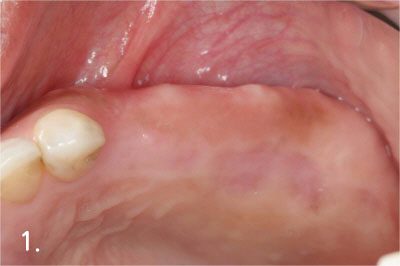

Gum bone is depressed after extraction